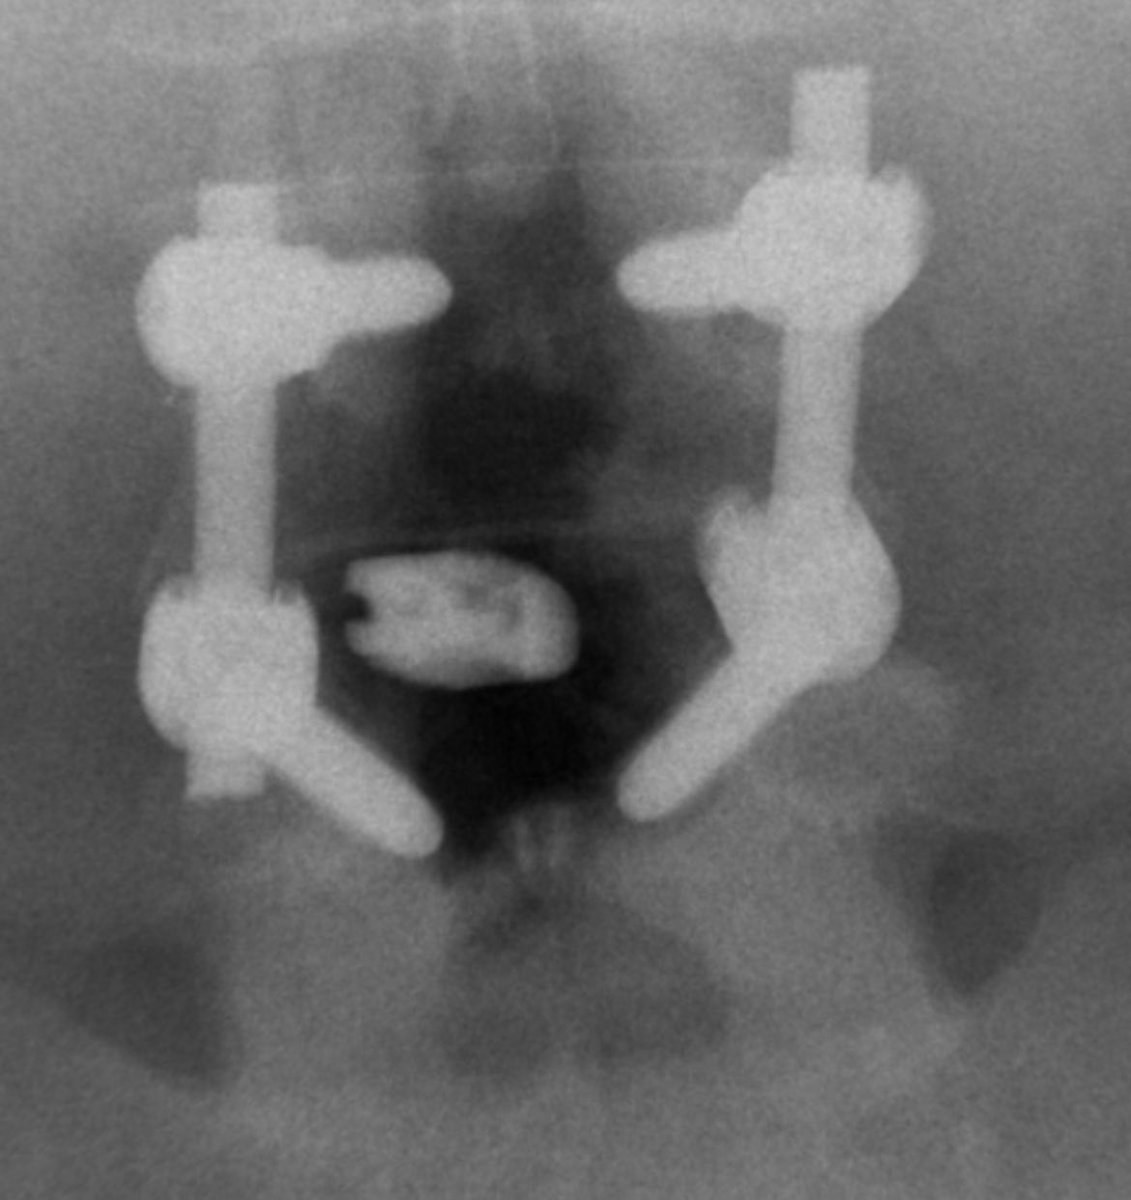

Case I performed recently.

One of the youngest awake brain tumor surgeries reported in the indexed literature so far.